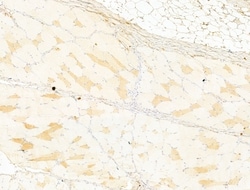

| Immunocytochemistry, Immunohistochemistry (Paraffin), Western Blot | |